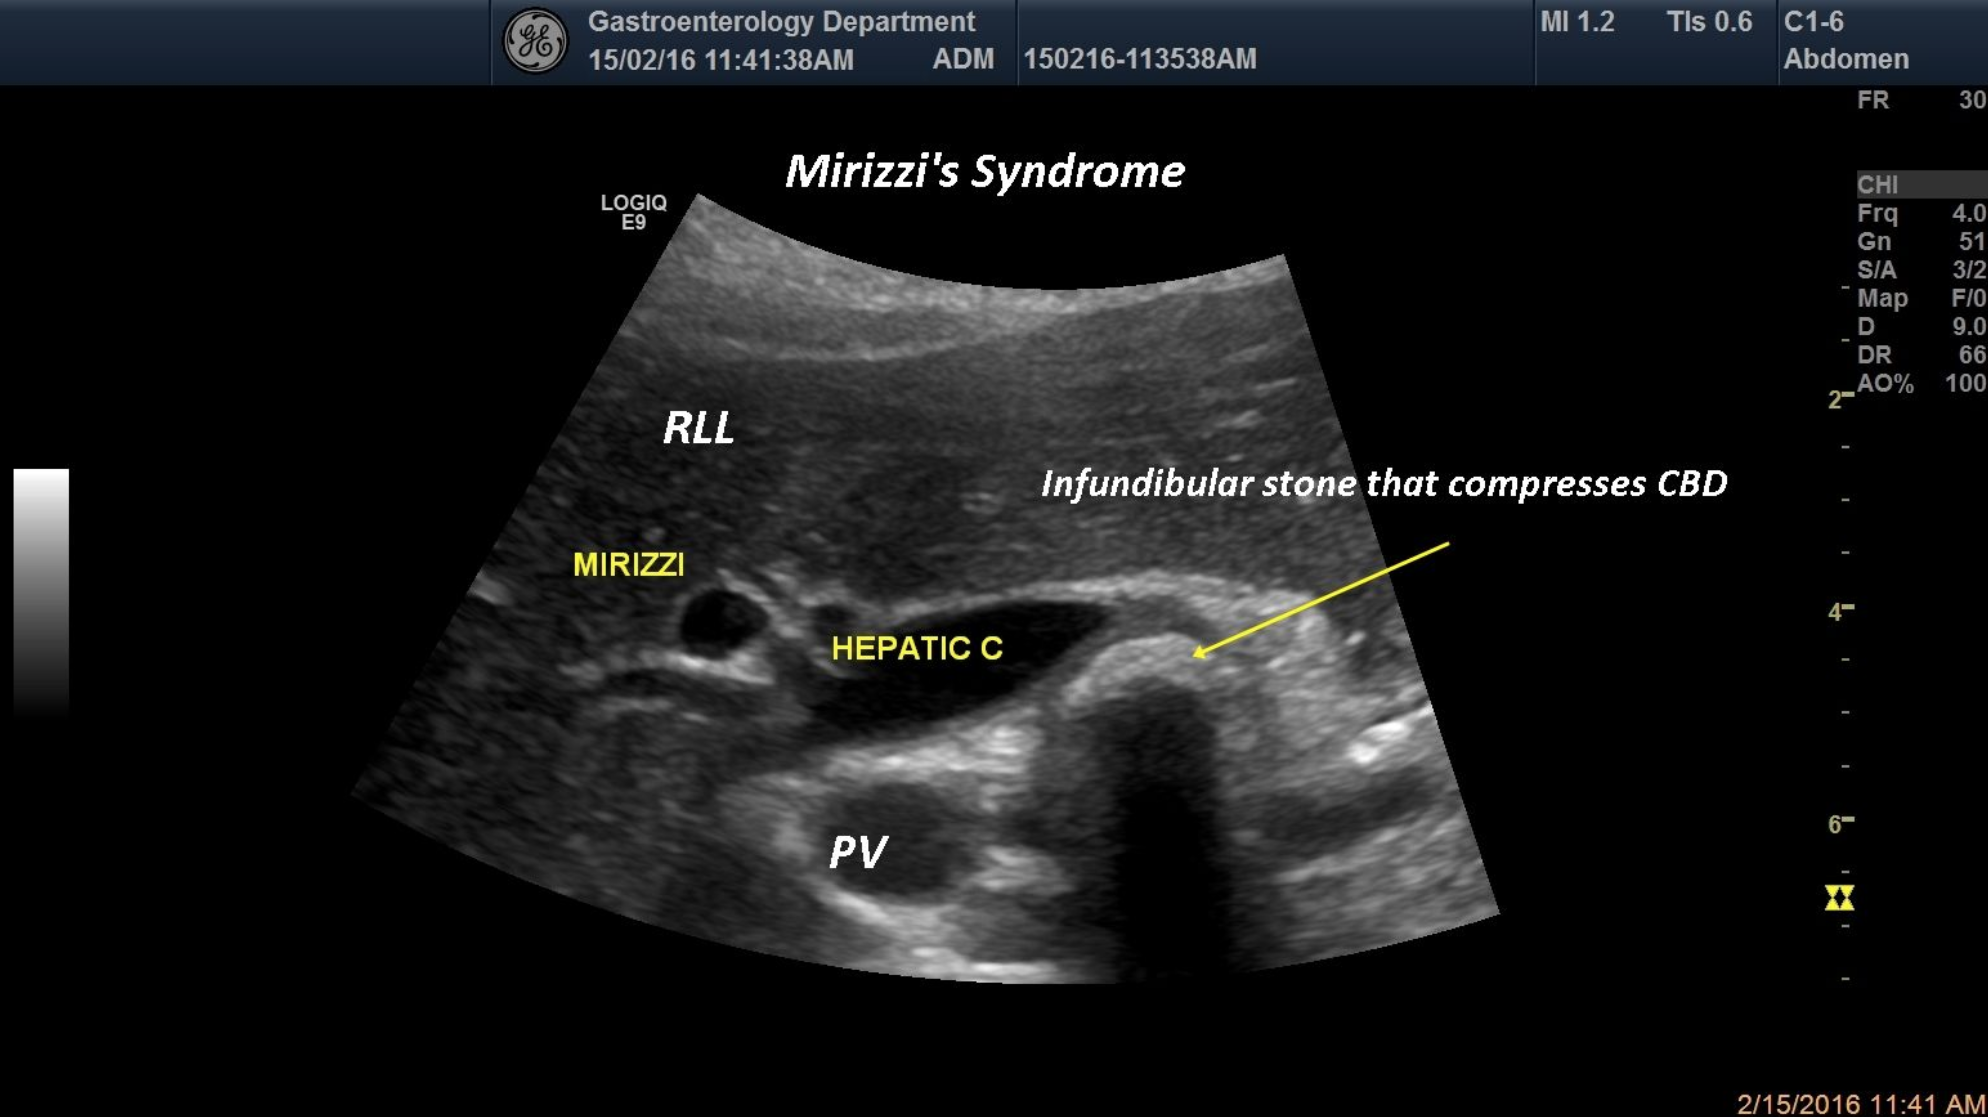

TITLE: Mirizzi syndrome

An 49-year-old patient was referred for jaundice and epigastric pain with acute onset. An infundibular impacted gallstone that compresses the CBD thus producing obstructive jaundice,was revealed by standard ultrasound.

Mirizzi syndrome,common bile duct, infundibular gallstone